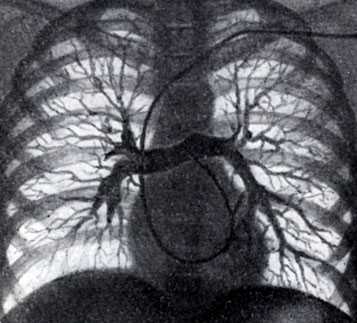

Применяют две методики ангиопульмонографии: общую и селективную; разновидностью селективной ангиопульмонографии является концевая ангиопульмонография.

Рис. 1. Общая ангиопульмонография. Контрастное вещество введено катетером. Видны контрастированные сосуды легких. Справа в области ключицы и вдоль позвоночника виден введенный в сердце катетер

Рис. 2. Селективная ангиопульмонография. Катетер (виден под ключицей, вдоль позвоночника и в области сердца) введен в верхнезональную артерию правого легкого. Видны контрастированные сосуды верхней зоны

Для осуществления общей ангиопульмонографии контрастное вещество в количестве 50—70 мл вводят внутривенно (обычно через локтевую вену) или в полость правого сердца (см. Ангиокардиография) при помощи введенного через вену катетера (рис. 1). При селективной ангиопульмонографии (рис. 2) контрастное вещество вводят в одну из ветвей легочного ствола; для этой цели катетер проводят через правое сердце в легочный ствол и далее в легочную артерию. Для контрастирования одного легкого применяют 20—30 мл контрастного вещества, для исследования одной зоны — 10—15 мл.

Различают три фазы контрастирования сосудов легких: артериальную, продолжающуюся 3—5 секунд, капиллярную, или паренхиматозную, продолжительностью в 1-3 секунды, и венозную, длящуюся 4—7 секунд. Для изучения легочного кровообращения проводят серию снимков на сериографе по следующей примерной программе: 2 снимка в 1 секунду в течение 3 секунд, затем 1 снимок в 1 секунду в течение 10 секунд.

Ангиопульмонография - метод рентгенологической диагностики состояния лёгочного кровообращения путём введения рентгеноконтрастных веществ в артерии лёгких. Выделяют общую и селективную ангиопульмонографию. При общей ангиопульмонографии контрастное вещество вводят в ствол лёгочной артерии, при этом заполняются все сосуды малого круга кровообращения. При селективной контраст вводится лишь в одну из ветвей лёгочной артерии и оценивается состояние кровотока только одного лёгкого или его доли.